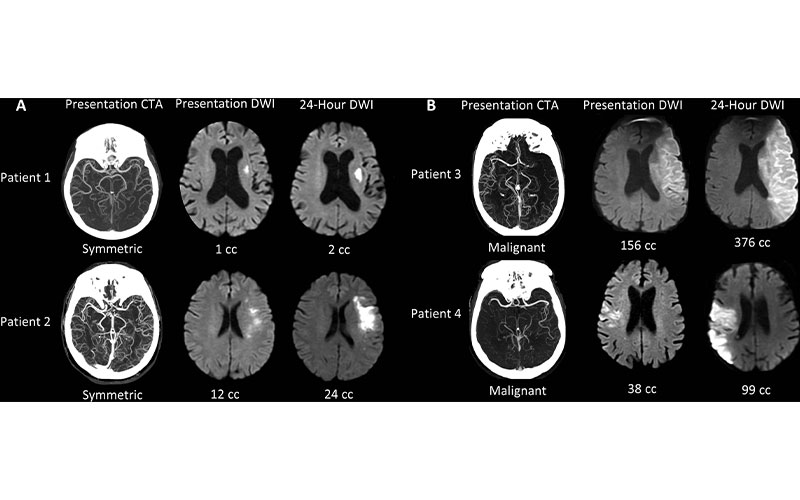

Collateral patterns at presentation CT angiography (CTA) and corresponding ischemic cores at presentation and 24-hour diffusion-weighted imaging (DWI). (A) Examples of patients with symmetriccollaterals. (B) Examples of patients with malignant collaterals. Patient 1 is an 84-year-old woman with National Institutes of Health Stroke Scale (NIHSS) score of 7 and symptom onset 4.1 hours prior. Patient 2 is a 70-year-old woman with NIHSS score of 7 and symptom onset 5.6 hours prior. Patient 3 is a 71-year-old man with NIHSS score of 21 and symptom onset 10.8 hours prior. Patient 4 is an 85-year-old man with NIHSS score of 6 and symptom onset 2.5 hours prior.

Regenhardt et al., Radiology 2021; 000:1–8 ©RSNA 2021